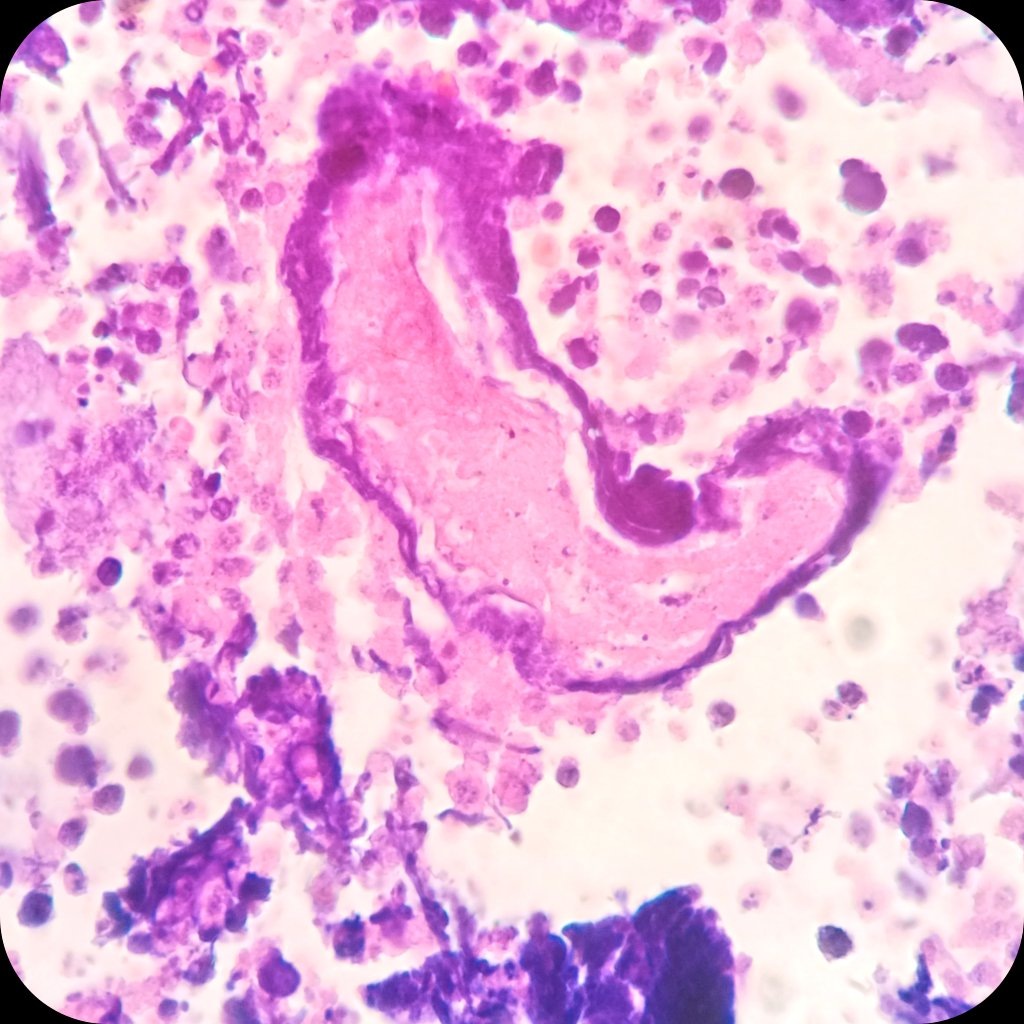

🧱 ΠšΠ»Π΅Ρ‚ΠΎΡ‡Π½Ρ‹ΠΉ Π±Π»ΠΎΠΊ

πŸ”¬ ΠœΠ΅Ρ‚Π°ΡΡ‚Π°Ρ‚ΠΈΡ‡Π΅ΡΠΊΠ°Ρ мСлкоклСточная ΠΊΠ°Ρ€Ρ†ΠΈΠ½ΠΎΠΌΠ°. ΠšΠ°Ρ‚Π΅Π³ΠΎΡ€ΠΈΡ 5 ΠΏΠΎ БиднСйской систСмС

πŸŒ€ Π€Π΅Π½ΠΎΠΌΠ΅Π½ Аззопарди (ΠΎΡ‚Π»ΠΎΠΆΠ΅Π½ΠΈΠ΅ Π±Π°Π·ΠΎΡ„ΠΈΠ»ΡŒΠ½ΠΎΠ³ΠΎ Π”ΠΠšβ€‘ΠΌΠ°Ρ‚Π΅Ρ€ΠΈΠ°Π»Π° ΠΈΠ· Π½Π΅ΠΊΡ€ΠΎΡ‚ΠΈΠ·ΠΈΡ€ΠΎΠ²Π°Π½Π½Ρ‹Ρ… ΠΊΠ»Π΅Ρ‚ΠΎΠΊ Π½Π° стСнках кровСносных сосудов).